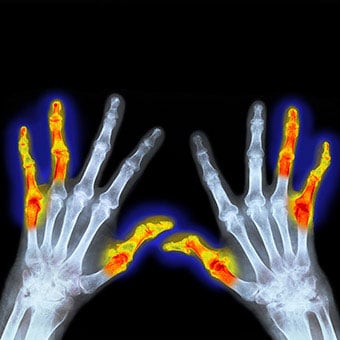

Joint deformity can occur from chronic rheumatoid arthritis. Deformity in rheumatoid arthritis occurs because the unchecked inflammation leads to erosions of cartilage and bone as well as ligament loosening (laxity).

- Early diagnosis and treatment of rheumatoid arthritis are critical to prevent permanent joint damage and joint deformity.

Usually, but not always, rheumatoid arthritis affects many joints. Classically, RA affects the small joints of the hands and wrists and balls of the feet. Also, not uncommonly, knees, elbows, hips, ankles, and shoulders can be inflamed.

Both sides of the body affected (symmetric)

Typically, the distribution of the joints involved in a person with rheumatoid arthritis is similar on both sides of the body. This symmetric joint involvement is a feature of classic rheumatoid arthritis. This does not mean that joint involvement is always symmetric, but it is common.

- Rheumatoid arthritis is characterized by inflammation in these joints.

- It also causes warmth, swelling, redness, and pain in varying degrees.